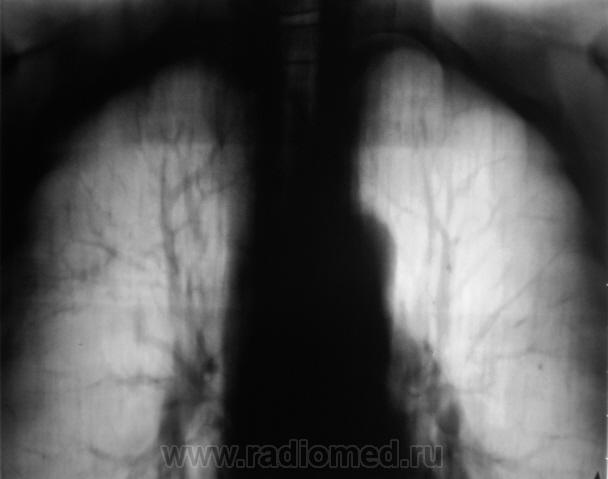

Пациент 4 месяца, по полной программе отлежал в областной конторе, ЦВК утвердило «инфильтративный». После выписки был направлен под надзор фтизиатра по месту жительства. Ниже иллюстрации после выписки.

Снимки сегодня.

Хорошая динамика, практически все рассосалось.

На мой взгляд на "семерке" еще дай-дай...